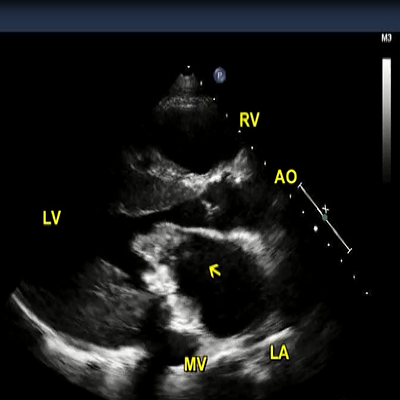

Echo: parasternal long axis view.

3 MB